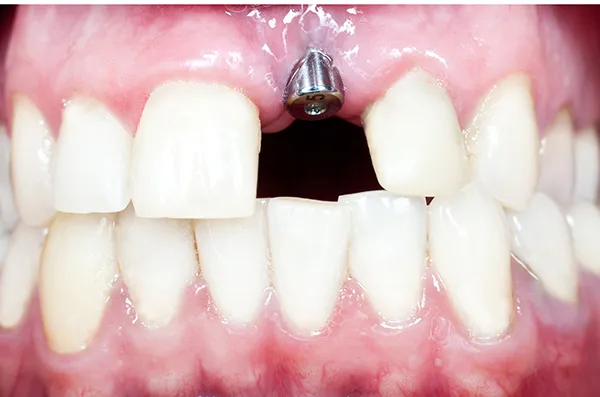

임플란트는 치아를 상실했을 때, 치아의 기능과 심미성을 회복하기 위해 사용하는 치과 치료 방법입니다. 임플란트는 인공 치아 뿌리를 잇몸뼈에 삽입한 후, 그 위에 인공 치아를 장착하는 방식으로 진행됩니다. 이는 자연 치아와 유사한 기능과 외관을 제공하며, 장기적으로 안정적인 결과를 보장합니다.

임플란트 시술은 몇 가지 단계를 거칩니다. 먼저, 환자의 구강 상태를 점검하고, 임플란트를 식립 가능한지 확인을 합니다. 그다음, 임플란트 뿌리를 잇몸뼈에 삽입하는 수술을 진행합니다. 수술 후에는 몇 개월 동안 임플란트가 뼈에 잘 고정되도록 기다리는 과정이 필요합니다. 마지막으로, 임플란트 위에 인공 치아를 장착하여 시술을 마무리합니다.